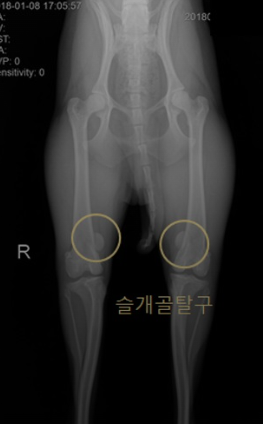

슬개골 탈구는 강아지의 무릎을 덮고 있는 작은 뼈인 슬개골이 원래 위치에서 벗어나는 현상을 말합니다. 슬개골은 무릎 관절의 움직임을 돕고 보호하는 역할을 하지만, 유전적인 요인이나 외상으로 인해 슬개골이 무릎 안쪽이나 바깥쪽으로 탈출하게 됩니다. 이때 슬개골 주변의 인대나 근육이 손상되고, 관절염이나 십자 인대 파열과 같은 다른 질환을 유발할 수 있습니다.

슬개골 탈구는 주로 소형견에게 흔하게 발생하는 질환으로, 포메라니안, 치와와, 말티즈 등이 취약합니다. 암컷보다 수컷이 잘 걸리며, 양쪽 다리에 동시에 발생할 수도 있습니다. 슬개골 탈구의 증상은 다음과 같습니다.

슬개골 탈구는 진행 정도에 따라 1기부터 4기까지 나뉘며, 1기는 가벼운 탈구로 슬개골이 자연적으로 제자리로 돌아가고, 4기는 심한 탈구로 슬개골이 제자리로 돌아가지 않고 통증이 심해집니다. 슬개골 탈구의 진단은 병원에서 촉진 검사나 X-선 검사를 통해 할 수 있습니다.